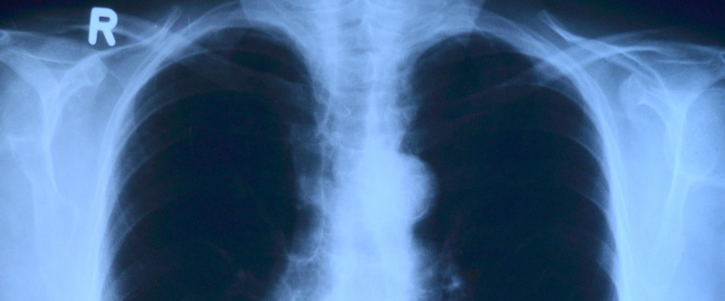

Algorithms could reduce turnaround time for chest X-ray reviews.

Using GE Healthcare’s Edison platform, the AI aims to help reduce the turnaround time it takes radiologists to review suspected pneumothorax, a type of collapsed lung.

If a patient is scanned on a device with Critical Care Suite, it will automatically analyze the images by searching for a pneumothorax, GE Healthcare claims. If suspected, an alert with the original X-ray is sent straight to the radiologist to review.